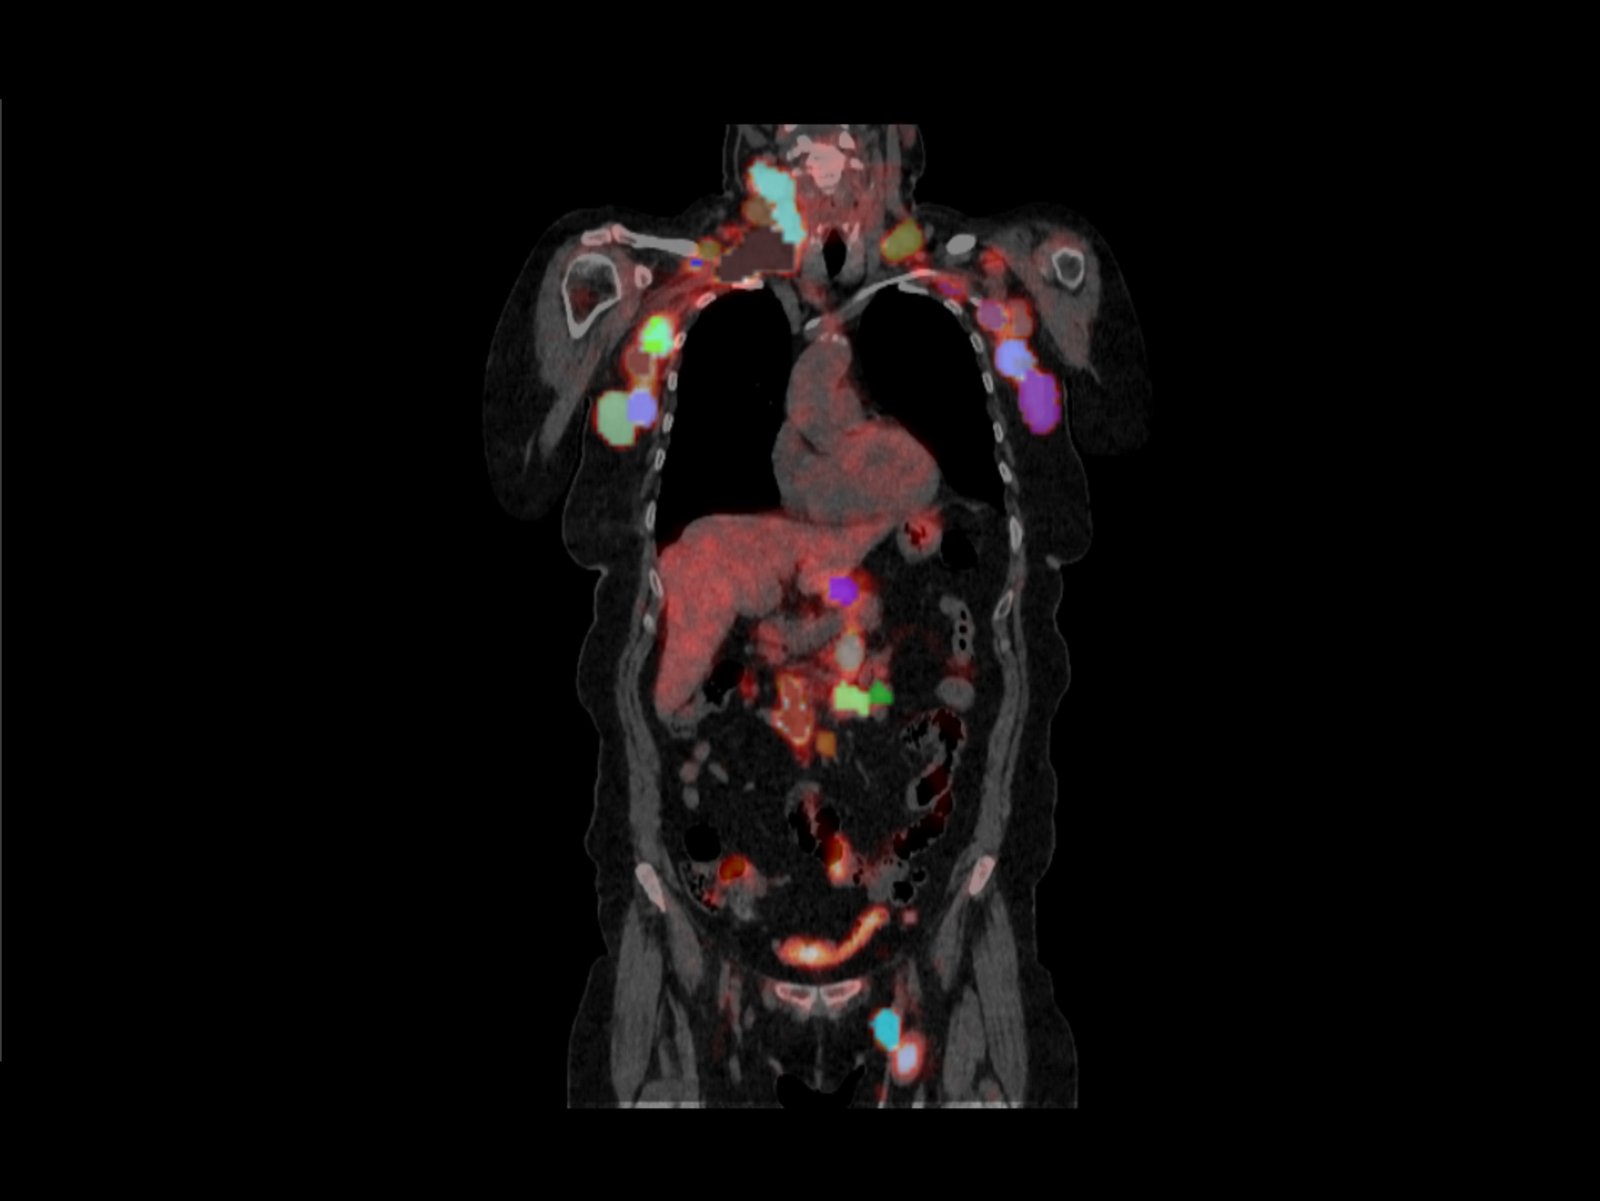

Sixty-five relapsed/refractory (R/R) B-cell lymphoma patients treated with CAR-T cells were included. All visible lesions from pre-treatment 18F-FDG PET/CT scans were segmented, and quantitative imaging features were extracted using the QP-Insights® platform. Quantitative imaging features were combined with relevant clinical variables to develop prognostic and predictive models.

The combined models significantly improved prediction accuracy compared to clinical or imaging features alone. For instance, the model for predicting ICANS achieved an area under the curve (AUC) of 0.830, and those for CAR-T response at 3 and 6 months showed AUCs of 0.754 and 0.818, respectively. Furthermore, the identified total metabolic tumor volume (MTVtotal) cut-off values effectively stratified patients by OS and PFS, with low MTVtotal associated with longer survival times.